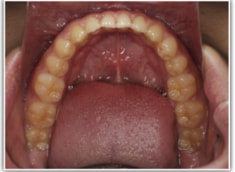

開咬(かいこう:オープンバイト)ケース

治療法:表の矯正(T21ブラケット)

(インプラントアンカーや外科矯正は行わず、エラスティックと機能訓練のみ)

治療後(2年2ヶ月後)